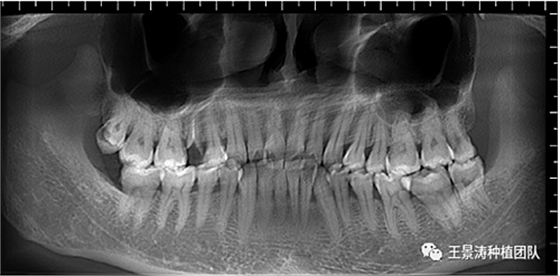

患者左側(cè)16慢性根尖周炎,17缺失。16根尖炎癥距上頜竇底較近,需內(nèi)提升,但是因?yàn)閮?nèi)提升后骨質(zhì)較薄所致植入深度過深,埋入式植入。17非埋入式種植。后期效果均可。